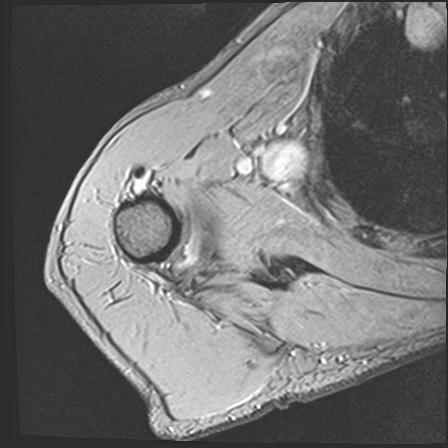

60058 3/9 11/4 右肩 2R+MRI 73歳男性 肩腱板損傷